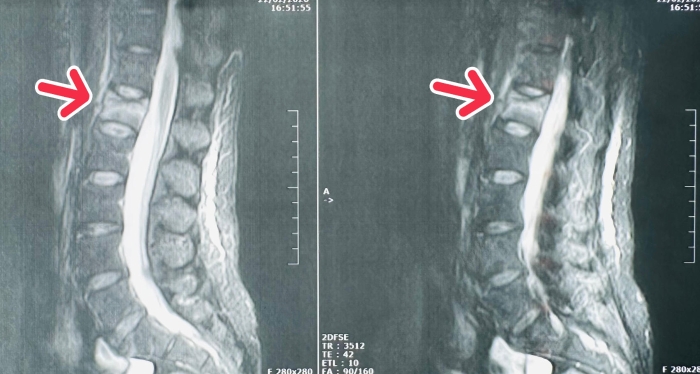

术前磁共振影像

患者女性,雪天走路不慎摔倒,臀部着地,当即感到腰背部剧痛,无法站立行走,后被紧急送往我院救治。行胸腰椎MRI(核磁共振成像)检查发现,腰1椎体新鲜压缩性骨折,考虑到患者对疼痛的耐受度及快速康复需求,姬传磊主任团队充分评估,并与患者家属沟通后,决定行手术治疗。